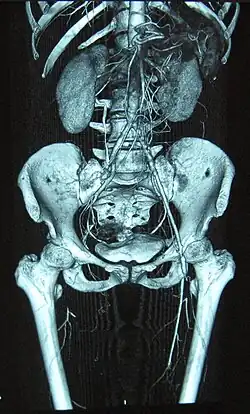

Angiogram wykonany metodą TK osoby cierpiącej na chorobę Buergera

Rozpoznanie opiera się na charakterystycznym wywiadzie (palenie tytoniu), wieku pacjenta, objawach (niedokrwienie dystalnych odcinków kończyn, owrzodzenia, ból spowodowany zajęciem nerwów[2]) oraz wykluczeniu innych chorób (układowy toczeń trzewny, sklerodermia, CREST, cukrzyca, zmiany miażdżycowe, zatorowość). Pomocnym badaniem jest angiografia, w której obraz przedstawia dystalne zamknięcia naczyń tętniczych o gładkich ścianach z charakterystycznymi naczyniami krążenia obocznego o korkociągowatym kształcie. Jako pomocnicze badanie można wykonać również test Allena, aczkolwiek nie jest to metoda odpowiednio czuła i swoista, aby wyłącznie za jej pomocą postawić rozpoznanie.